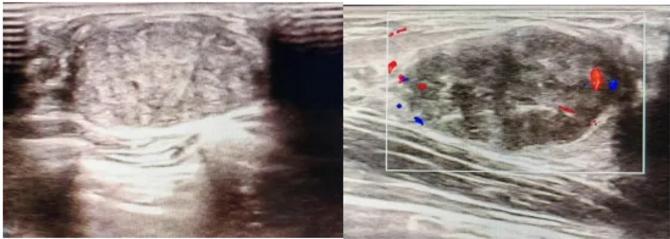

三、彩超檢查:無創(chuàng)檢查的“黃金眼”

高分辨率:可清晰顯示腫塊形態(tài)、血流信號,敏感度達80%-90%。

2.彩超報告關(guān)鍵指標(biāo)

形態(tài):良性多呈橢圓形或分葉狀,邊界光滑。

縱橫比: 良性通常<1(橫徑>縱徑) 。

血流信號:纖維瘤血流較少,惡性常伴豐富雜亂血流。

鈣化:粗大鈣化多為良性,細小簇狀鈣化需警惕惡性。

BI-RADS分級:2-3類提示良性,4類以上需進一步檢查。

典型表現(xiàn):

橢圓形低回聲團塊,包膜完整,內(nèi)部回聲均勻,后方回聲增強,周邊無“蟹足樣”浸潤。